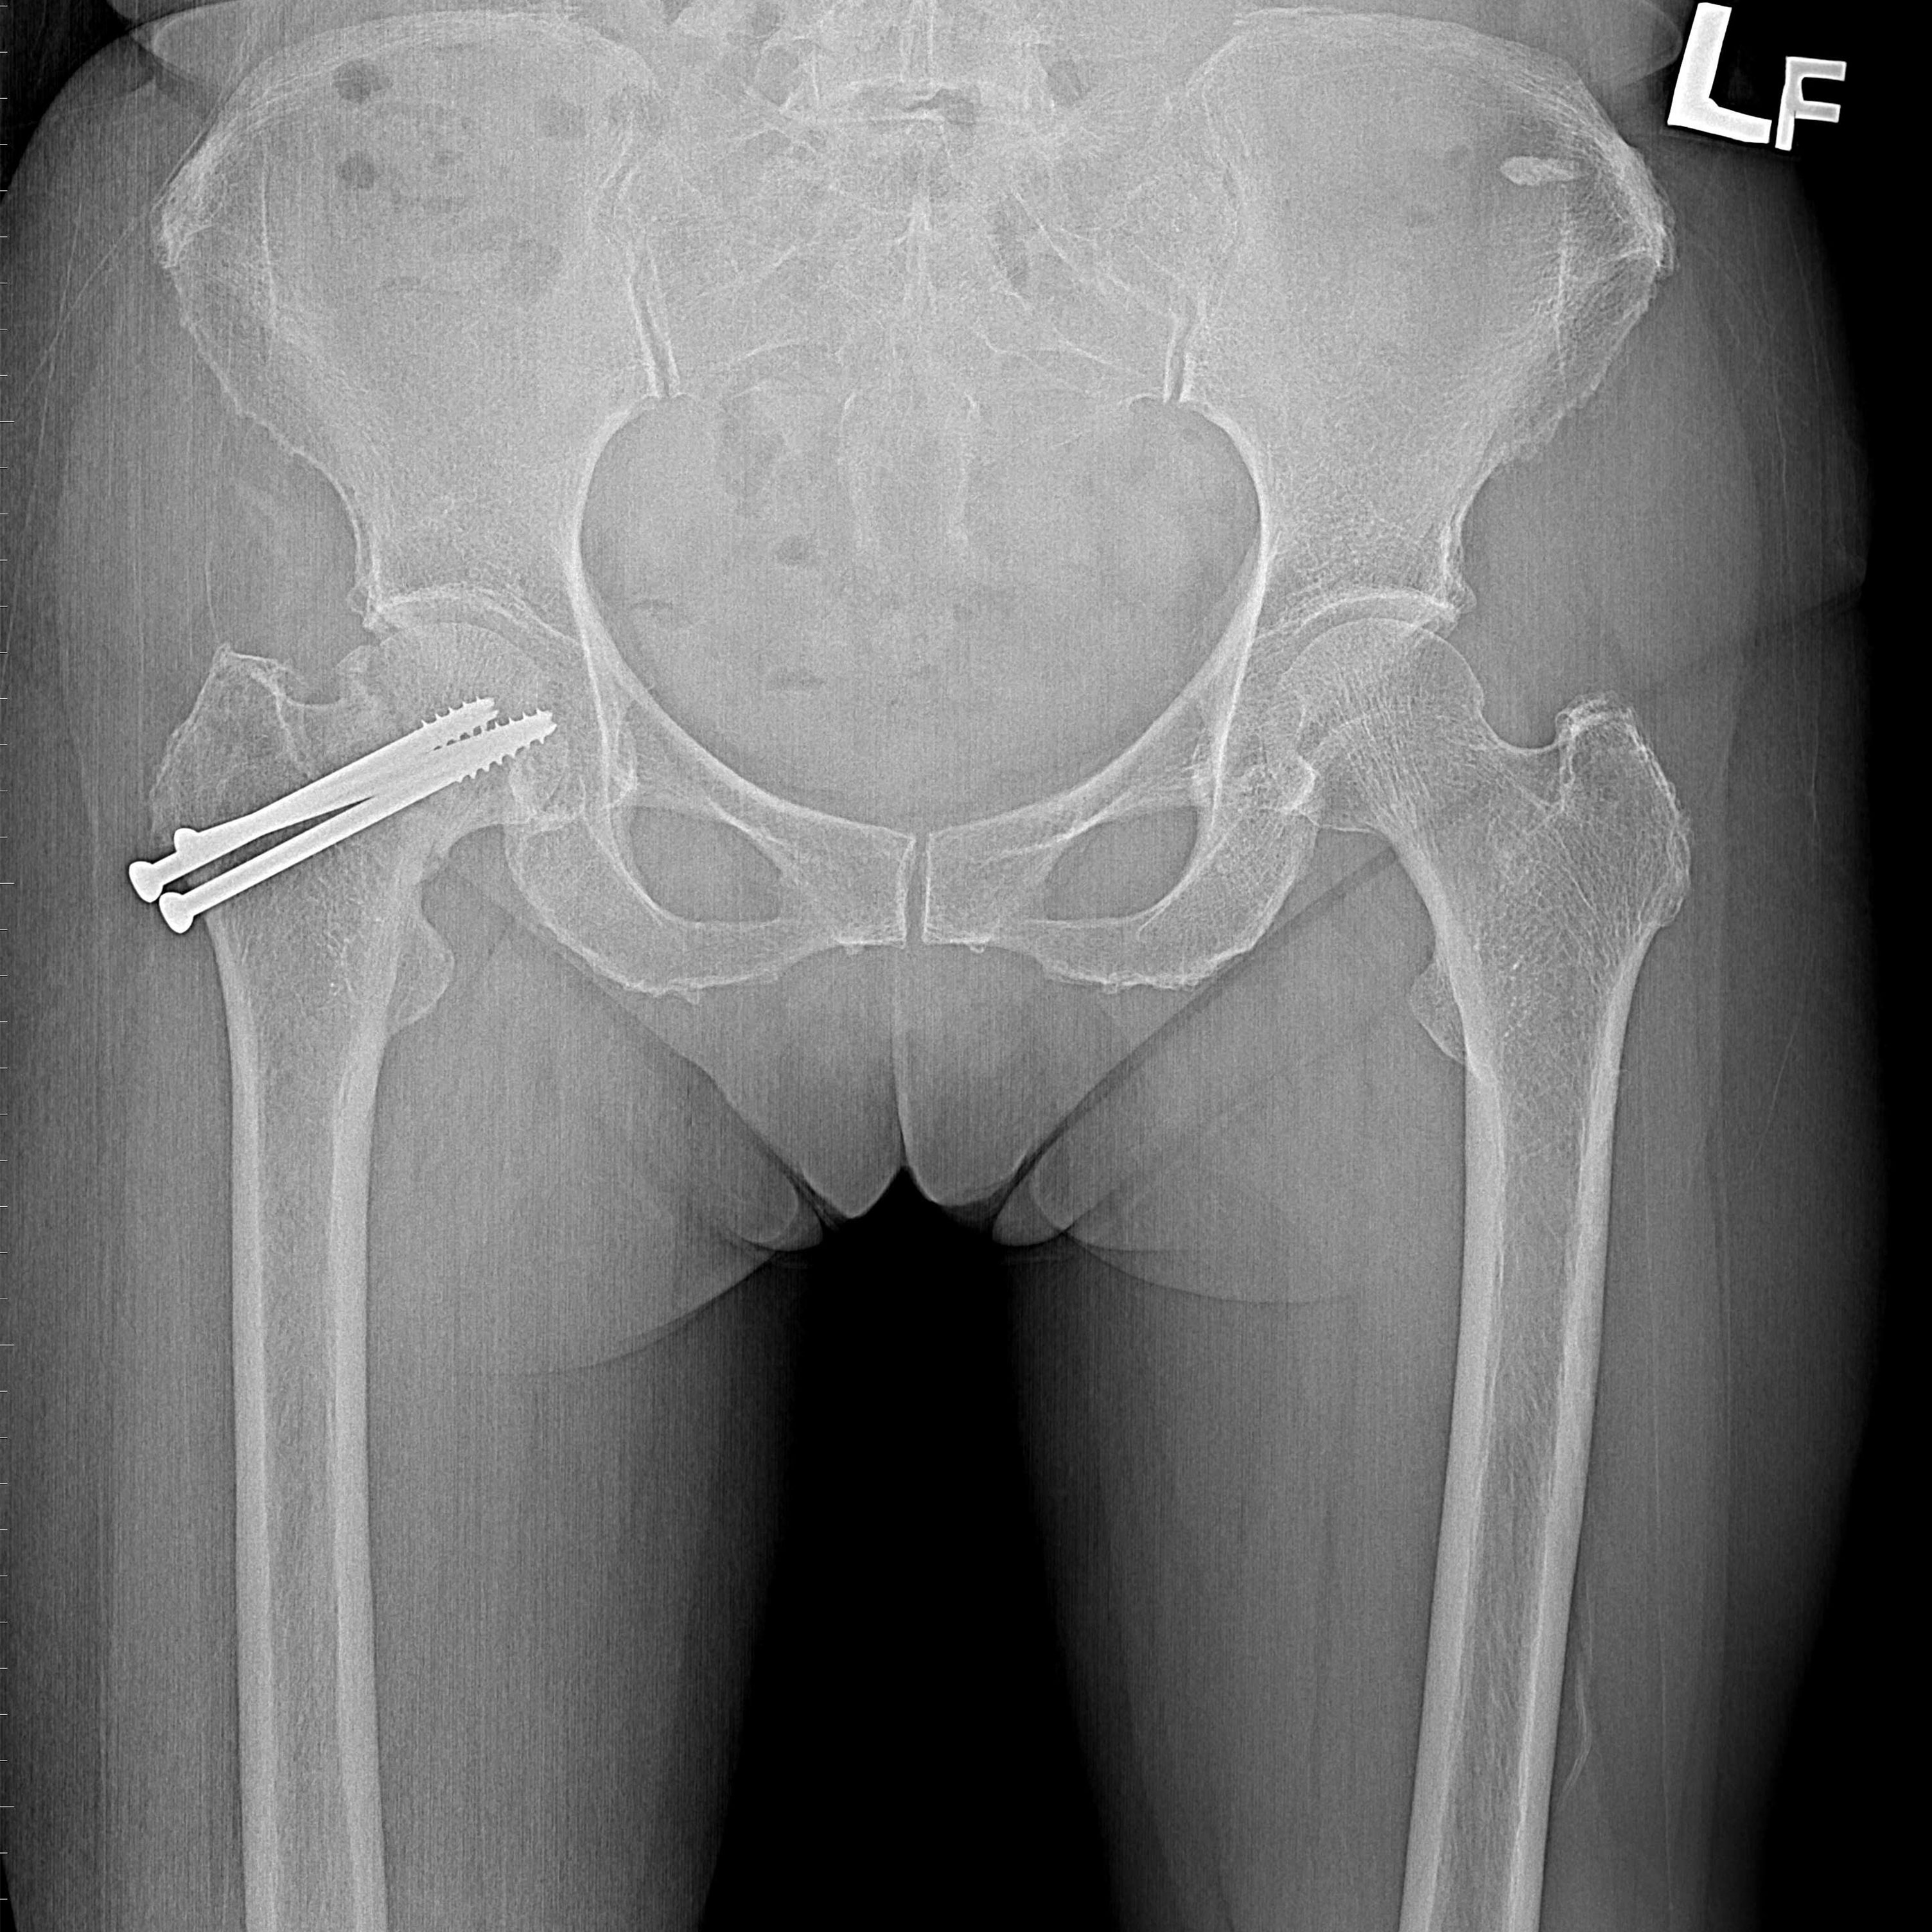

機器手臂手術 首頁 案例分享 髖關節手術 機器手臂手術 72歲 楊女士 退化性關節炎 術前 術後 60歲 彭先生骨股頭壞死 術前 術後 53歲 王女士退化性關節炎(DDH先天發育不全 CROWE TYPE 2) 術前 術後 83歲林女士退化性關節炎 術前 術後 83歲林女士退化性關節炎 術前 術後 楊女士 70歲 術前 術後 蔡女士 60歲 術前 術後